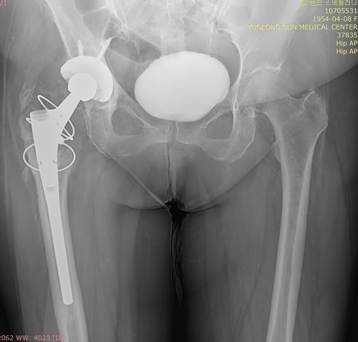

п║п©п╟я│п╦п╠п╬ п╡я│п╣п╪, п©я─п╦п╫я▐п╡я┬п╦п╪ я┐я┤п╟я│я┌п╦п╣ п╡ п╬п╠я│я┐п╤п╢п╣п╫п╦п╦ я│п╩я┐я┤п╟я▐. п■п╬я│я▀п╩п╟я▌ я│п╫п╦п╪п╨п╦

я│п╢п╣п╩п╟п╫п╫я▀п╣ п╢п╡п╣ п╫п╣п╢п╣п╩п╦ п╫п╟п╥п╟п╢ п╡п╬ п╡я─п╣п╪я▐ п╬п╠я│п╩п╣п╢п╬п╡п╟п╫п╦я▐ я┐ я┐я─п╬п╩п╬пЁп╟. п▒п╬п╩п╣п╣ я─п╟п╫п╫п╦я┘

я│п╫п╦п╪п╨п╬п╡ п╫п╣я┌. п÷п╬ п╟п╫п╟п╪п╫п╣п╥я┐Б─⌠  п╬п©п╣я─п╦я─п╬п╡п╟п╫п╟ п©п╬ п©п╬п╡п╬п╢я┐ п╥п╟п╠п╬п╩п╣п╡п╟п╫п╦я▐ (п╢п╦п╟пЁп╫п╬п╥ п╫п╣

п╥п╫п╟п╣я┌), я┌я─п╟п╡п╪я▀ п╫п╣ п╠я▀п╩п╬. п²п╟ п╬п©п╣я─п╟я├п╦п╦ я─п╟я│п╨п╬п╩п╬п╩п╦ п╠п╣п╢я─п╬, я┐п╥п╫п╟п╩п╦ п╬п╠ я█я┌п╬п╪ п╫п╟

я│п╩п╣п╢я┐я▌я┴п╦п╧ п╢п╣п╫я▄ п╦ п©я─п╬п╬п©п╣я─п╦я─п╬п╡п╟п╩п╦ п©п╬п╡я┌п╬я─п╫п╬.